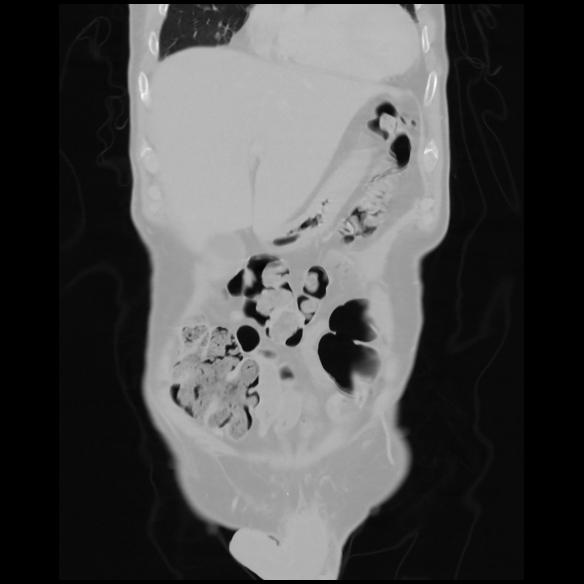

6 CUERPO,CE,Coronal,3.000,CUERPO,Coronal,